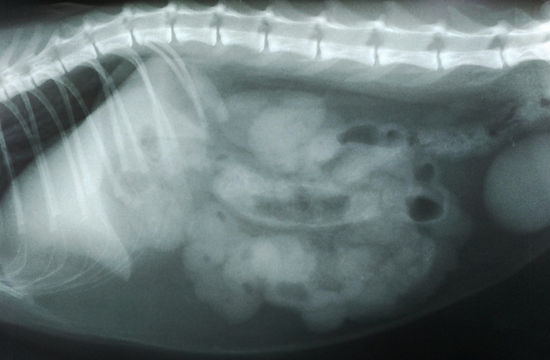

ESTUDIO RADIOGRÁFICO

Se realizan posiciones RX laterolateral izda. y ventrodorsal, no viendo imágenes claramente patológicas excepto posible compatibilidad con cuerpo extraño lineal en intestino delgado (moderado rosario con pequeñas bolsas de gas), aumento de densidad en zona epigástrica, imagen de tierra en estómago/ vesícula biliar y gas/ heces moderados en colon.